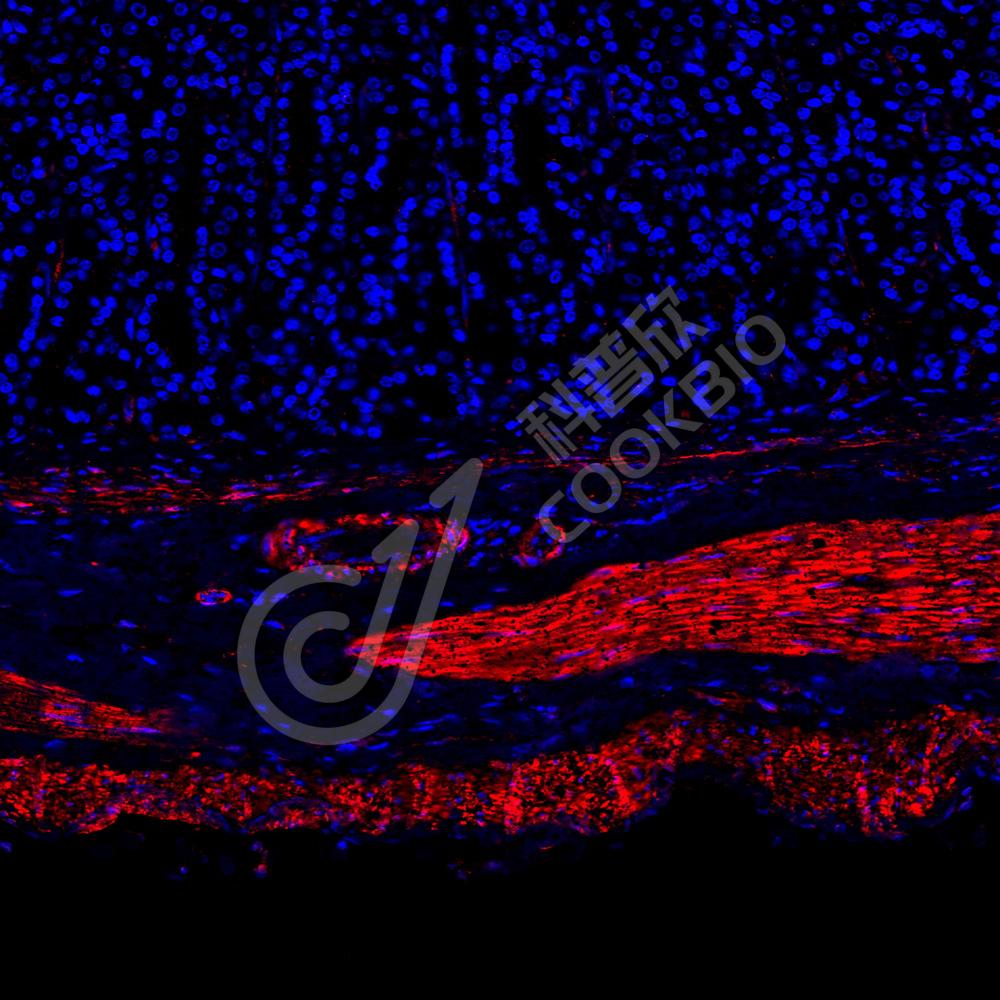

IF检测Desmin蛋白(货号 K236225)(红色).

样品: 小鼠胃, 4%多聚甲醛 (货号KSG1101) 固定12-24小时.

抗原修复: 柠檬酸抗原修复液(干粉, pH 6.0) (KSG1201), 高压锅均匀喷气计时2分钟.

封闭: 3% BSA(货号KSGC305010)的PBS溶液, 室温孵育30分钟.

—抗: 1: 1300稀释, 4℃ 孵育过夜.

二抗: Cy3标记山羊抗小鼠IgG (H+L) (货号KB63903), 1: 300稀释, 室温孵育1小时.